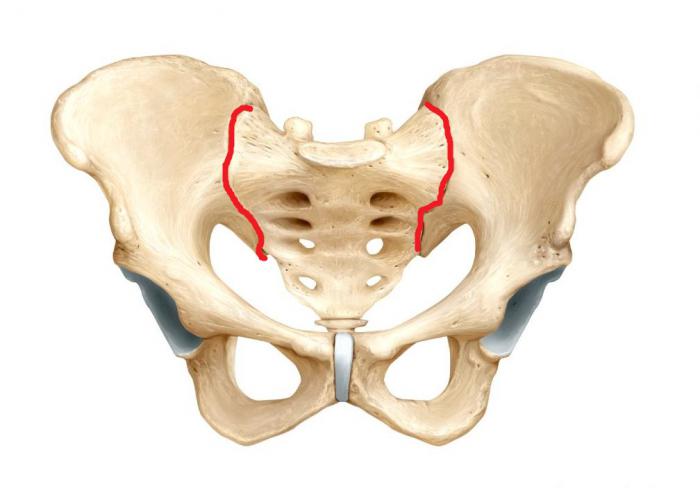

Одно- и двухсторонний

В большинстве случаев воспаление крестцово-подвздошного сустава имеет односторонний характер. При локализации патологического процесса справа речь идет о правостороннем, слева – левостороннем сакроилеите.

2-х сторонний сакроилеит – что это такое и чем он опасен? Для заболевания характерно одновременное вовлечение в воспалительный процесс сразу обоих крестцово-подвздошных суставов. Данная патология нередко является признаком болезни Бехтерева, которая имеет тяжелое течение и приводит к ранней инвалидизации.

На ранней стадии болезни рентгенологические признаки либо отсутствуют, либо практически незаметны. Очаги остеосклероза, сужение межсуставных щелей и признаки анкилозов появляются лишь на 2 и 3 степени сакроилеита. Диагностировать болезнь в самом ее начале можно с помощью МРТ. Большинство пациентов с сакроилеитом обращается к врачу лишь на 2 стадии болезни, когда боли начинают вызывать дискомфорт.